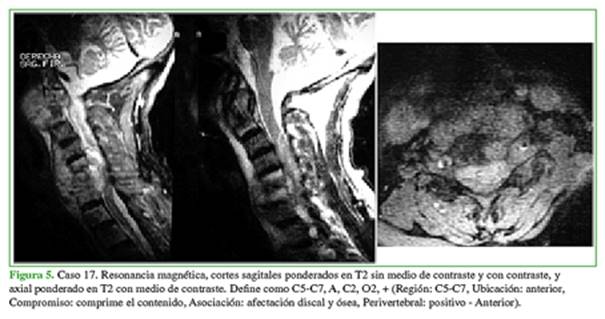

El coeficiente kappa de Cohen sobre el acuerdo intra- e interobservador global fue de 0,76, lo que se considera una muy buena concordancia de reproducibilidad. Los valores de cada parámetro en particular fueron: R 0,94; U 0,88; C 0,55, según la ventana de la resonancia y el uso de medio de contraste; A 0,67 y P 0,77. Los tres primeros parámetros dan una noción de volumen que, en un próximo proceso, se podría relacionar con la toma de una decisión terapéutica y los dos últimos indican la presencia de focos infecciosos vertebrales por fuera del conducto (Figuras 4-6).

La ventana ponderada en T2 con gadolinio fue la imagen con mayor acuerdo entre los evaluadores (kappa >0,87) en todos los cortes, seguida de la T2 sin contraste, STIR y, por último, T1 sin contraste.